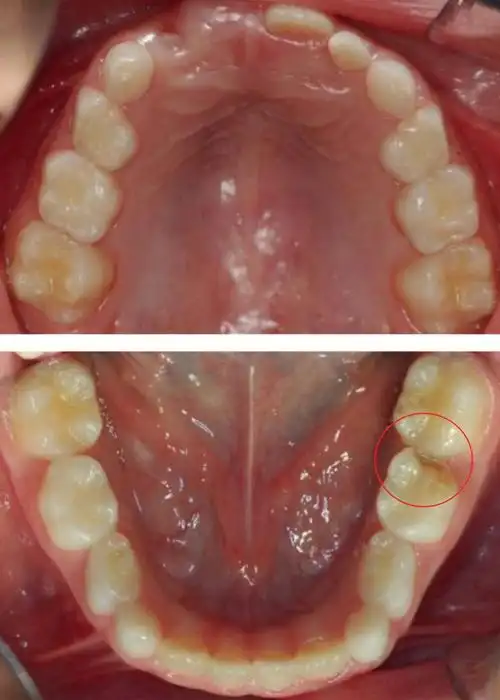

(上颌和下颌弓的正面临床视图)口腔内检查发现左侧第二乳磨牙有龋齿